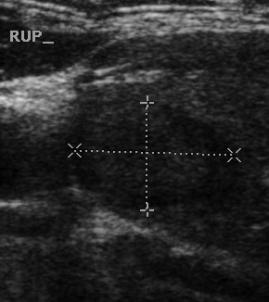

- Tiroid iltihabı (Hashimoto)

- Hashimato'da lazer tedavisi: İlaç dozlarının azaltılması veya kesilmesi ve kilo kontrolü !!!